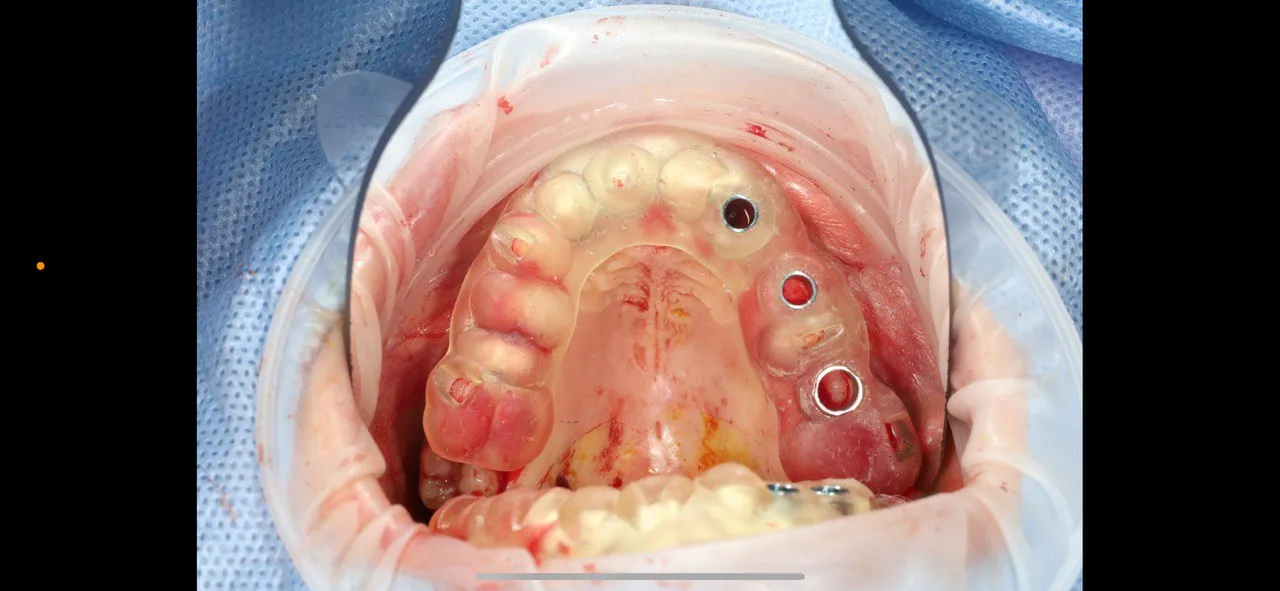

Full-Arch Implant Rehabilitation

All-on-4 surgical guide for complete upper arch restoration